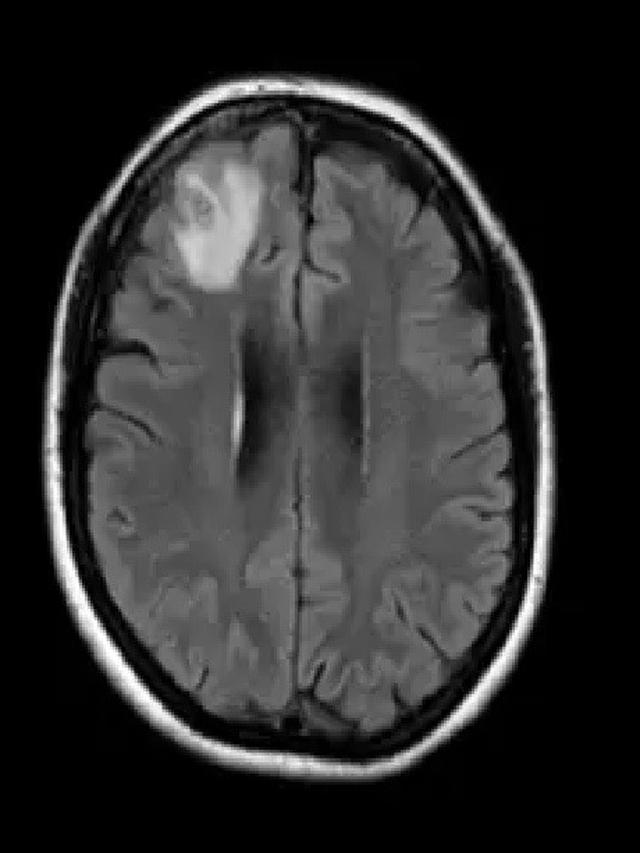

Sejak tahun 2021, wanita tersebut telah mengalami berbagai masalah kesehatan termasuk pneumonia, sakit perut, diare, batuk kering, demam, dan keringat malam. Pada tahun 2022, gejalanya berkembang menjadi depresi dan kelupaan, yang mengakibatkan dokter memerintahkan pemindaian MRI otak. Hasil pemindaian ini mengungkapkan keberadaan kelainan yang memerlukan tindakan pembedahan.

Namun, yang membuat peristiwa ini semakin tidak biasa adalah saat operasi dilakukan, tim bedah menemukan cacing gelang parasit berukuran 8 cm berwarna merah cerah yang hidup di otak wanita tersebut. Cacing ini dikenal sebagai Ophidascaris robertsi yang sebelumnya hanya ditemukan pada ular piton karpet. Ini merupakan kasus pertama kali cacing ini ditemukan hidup di dalam tubuh manusia.